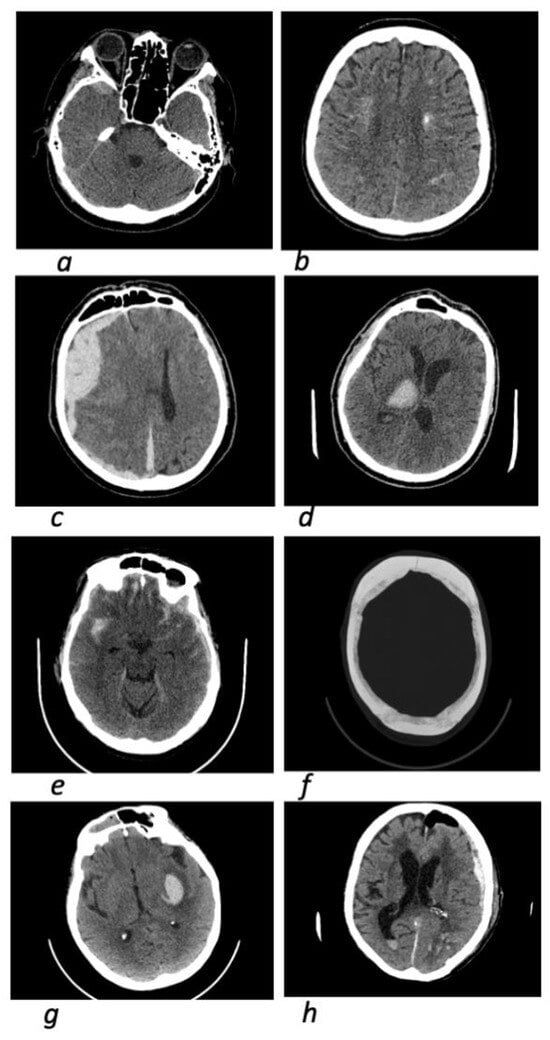

- Intracerebral hemorrhage (ICH): a CT study reveals a hyperdense area (from +45–50 to 90 HU) of any location and shape, heterogeneous or homogeneous inside the brain tissue, which can rupture into the intraventricular spaces (intraventricular hemorrhage);

- Subarachnoid hemorrhage (SAH): in CT scans, hyperdense areas (from +45–50 to 90 HU) of various shapes and sizes are found in the subarachnoid spaces and cisterns of the brain;

- Subdural hemorrhage (SDH): on CT images, crescent-shaped hyperdense areas (from +45–50 to 90 HU), homogeneous or heterogeneous in structure, are detected in the subdural space, or crescent-shaped isodense ones (~35–40 HU), corresponding to the subacute stage of SDK;

- Epidural hemorrhage (EDH): a CT study reveals biconvex (lenticular) hyperdense areas (from +45–50 to 90 H units) in the epidural space, often heterogeneous in structure [24].